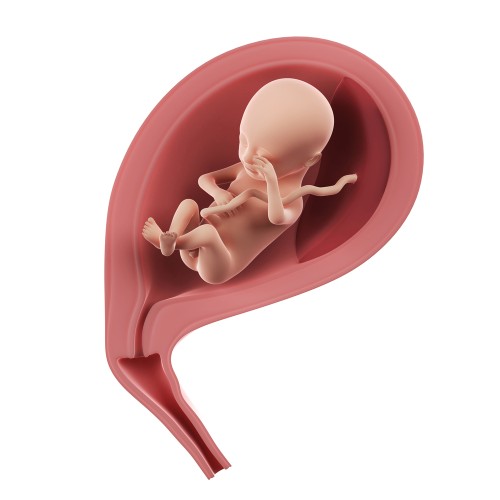

Матка за последнюю неделю значительно увеличилась и теперь по размерам напоминает небольшую дыню. Высота её дна составляет 18-19 см, и матка расположена на несколько пальцев ниже пупка. Стенки матки и её связочный аппарат постепенно растягиваются, при этом некоторые волокна могут удлиниться в пять раз за весь период беременности.

Что происходит в животе будущей мамы?

С увеличением размеров матки возрастает давление на соседние органы и ткани, а также нагрузка на позвоночник. Это может вызвать болезненные ощущения, связанные с ущемлением седалищного нерва, а также дискомфорт в пояснице и спине. У некоторых беременных женщин возникает боль в районе пупка из-за давления матки на эту область. Для облегчения неприятных ощущений и болей на данном этапе беременности полезен специальный бандаж, который поможет предотвратить множество возможных осложнений.

К концу восемнадцатой недели беременности размер плода достигает 12-14 см, а его масса увеличивается до 150 г. По своим габаритам он напоминает манго. Пропорции тела становятся более гармоничными, продолжается окостенение скелета, а фаланги пальцев рук и ног завершают формирование. На подушечках пальцев уже проявляется уникальный рисунок.